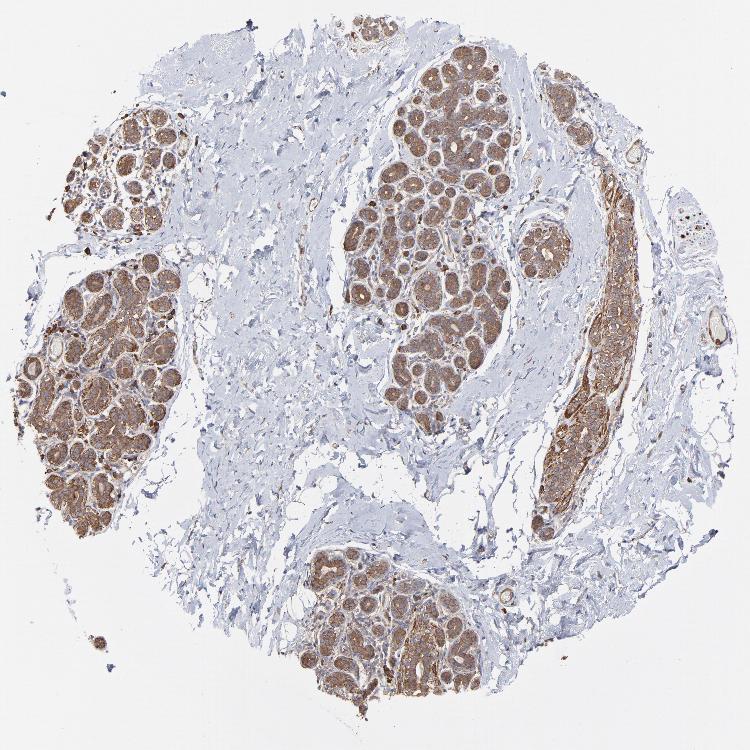

BREAST - Antibody stainingi

Antibody staining in the annotated cell types in the current human tissue is reported as not detected, low, medium, or high, based on conventional immunohistochemistry profiling in selected tissues. This score is based on the combination of the staining intensity and fraction of stained cells.

Each image is clickable and will lead to virtual microscopy that enables deeper exploration of all samples and also displays staining intensity scores, fraction scores and subcellular localization as well as patient and tissue information for each sample.

Antibody HPA002117

Adipocytes Not detected

Glandular cells Medium

Myoepithelial cells Medium